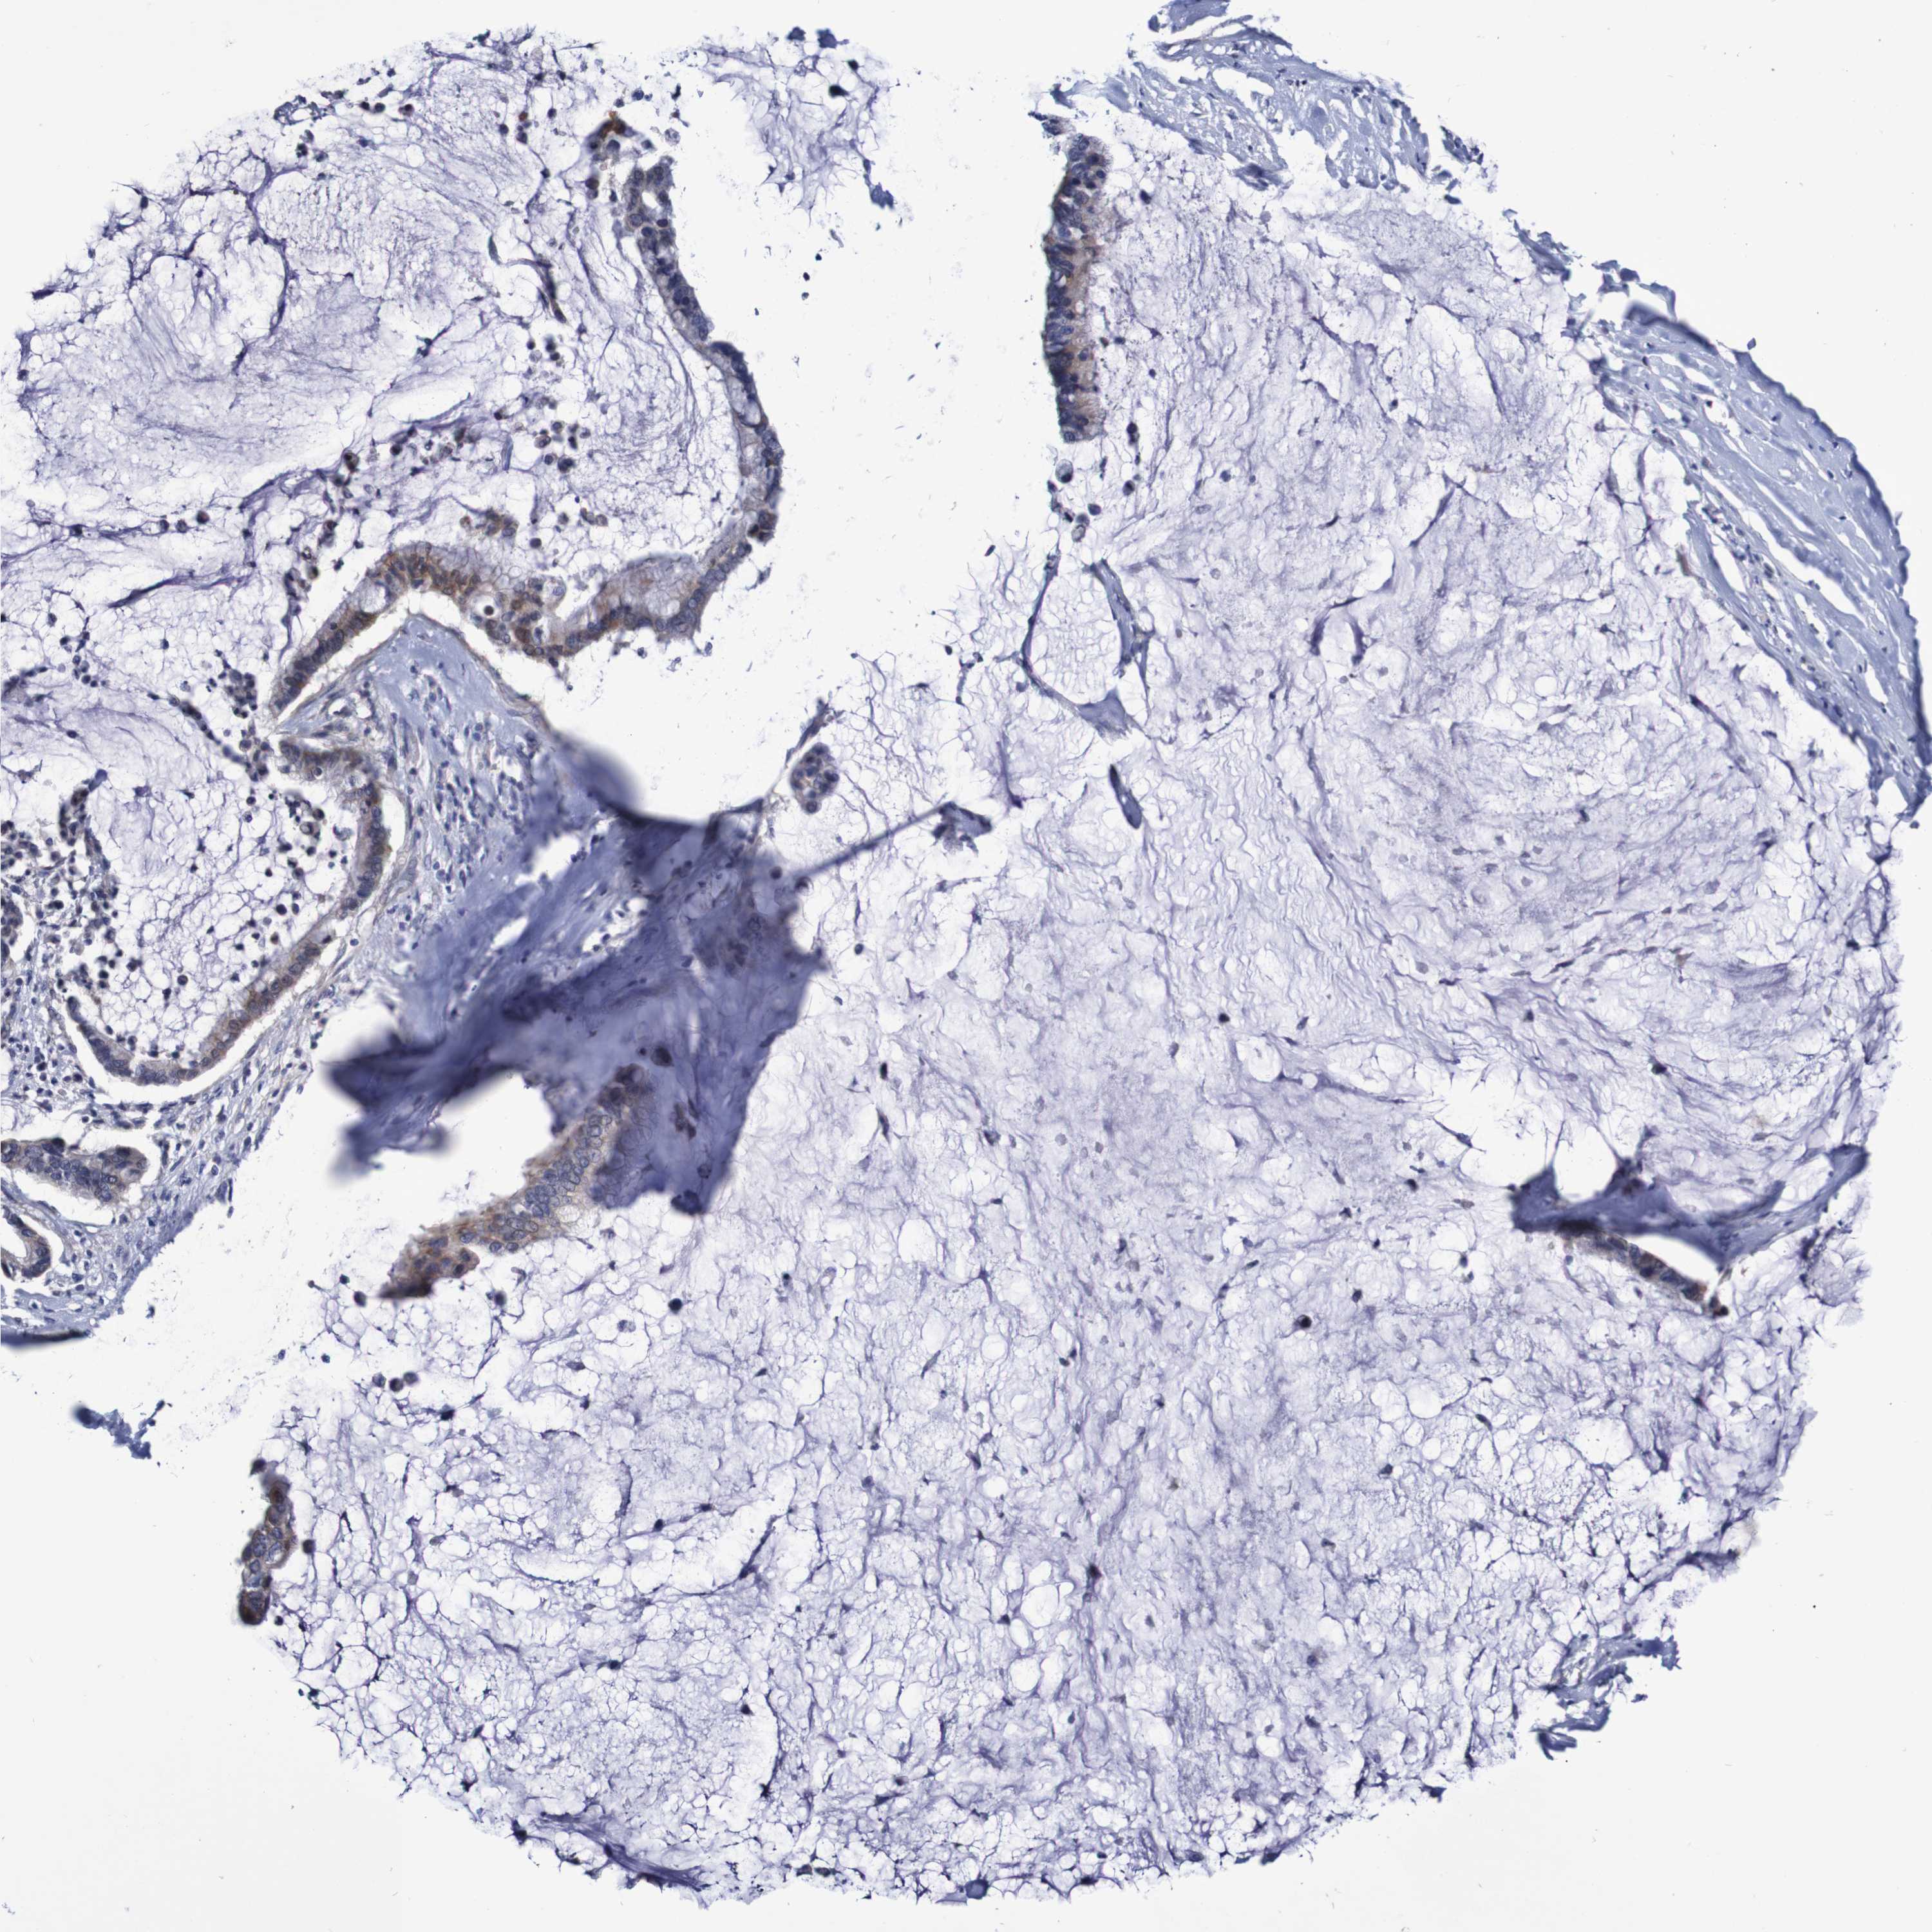

PANCREATIC CANCER - Protein expressioni

A mouse-over function shows sample information and annotation data. Click on an image to view it in a full screen mode. Samples can be filtered based on level of antibody staining by selecting one or several of the following categories: high, medium, low and not detected. The assay and annotation is described here.

Note that samples used for immunohistochemistry by the Human Protein Atlas do not correspond to samples in the TCGA dataset.

Antibody stainingi

Antibody staining in the annotated cell types in the current human tissue is reported as not detected, low, medium, or high, based on conventional immunohistochemistry profiling in selected tissues. This score is based on the combination of the staining intensity and fraction of stained cells.

Each image is clickable and will lead to virtual microscopy that enables deeper exploration of all samples and also displays staining intensity scores, fraction scores and subcellular localization as well as patient and tissue information for each sample.

Antibody HPA007982

Antibody HPA011933

Staining

High

Medium

Low

Not detected

Intensity

Strong

Moderate

Weak

Negative

Quantity

>75%

75%-25%

<25%

None

Location

Nuclear

Cytoplasmic/membranous

Cytoplasmic/membranous,nuclear

Adenocarcinoma, NOS

Adenocarcinoma, metastatic, NOS